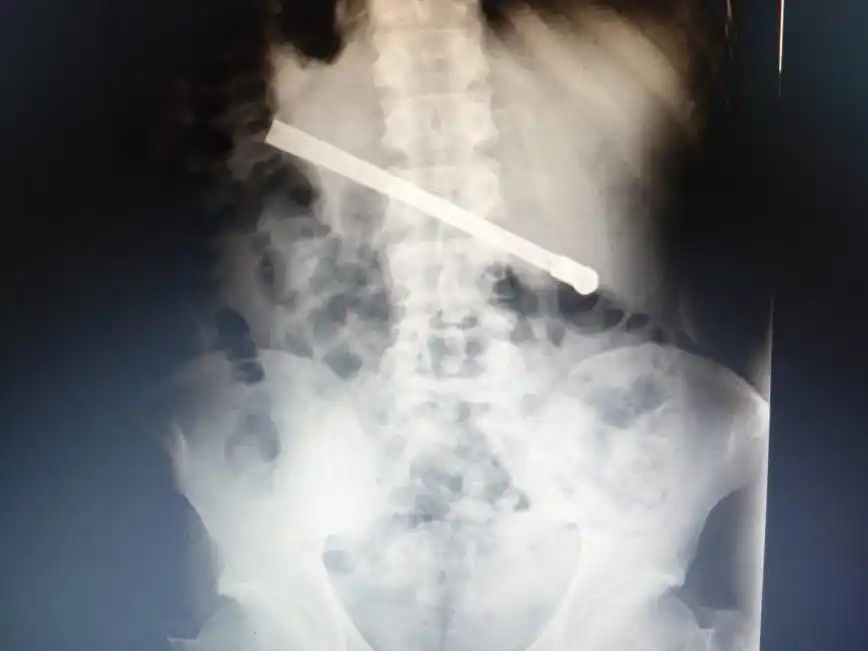

Un preso de 35 años condenado por abuso sexual tuvo que ser operado luego de que se tragara una bombilla de mata y la tuviera atravesada en el tórax.

En la Unidad Penitenciara de 27 de Febrero al 7800, le hicieron una radiografía en la que se mostró que el hombre se había tragado una bombilla y ahora la tenía alojada en la cavidad torácica.

En consecuencia, fue derivado al Hospital Eva Perón, donde fue operado con éxito para luego quedar en observación hasta que se lo pueda derivar nuevamente al CPR.